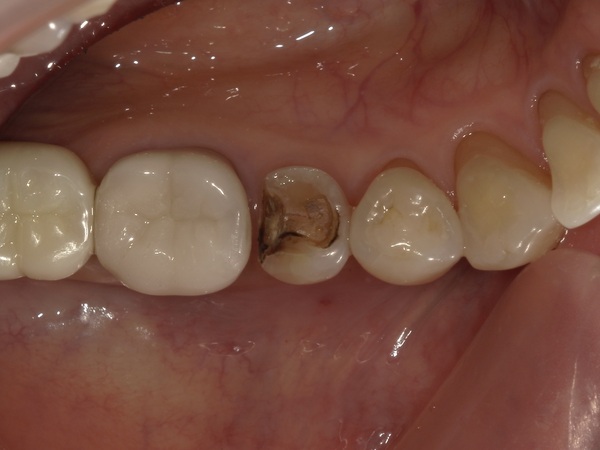

①銀歯の除去

部分麻酔を行い、銀歯を外しました。こちらが銀歯を外した状態の写真になります。

銀歯の下で虫歯が茶色く広がっているのが分かります。虫歯を染める薬液を使いながら、丁寧に虫歯を取り除きました。

今回のケースでは虫歯は神経まで達しておらず、神経を残すことができました。